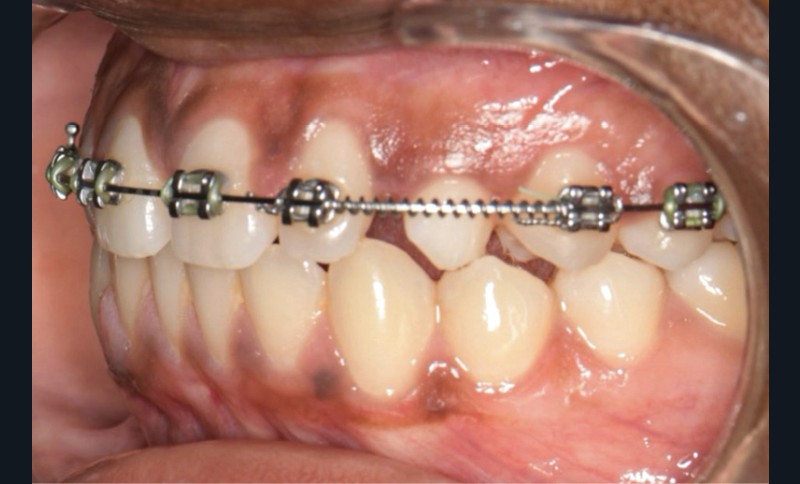

Le traitement orthodontique a été réalisé en technique vestibulaire multi-attaches 0,022’’ x 0,028’’. Après l’alignement et le nivellement de l’arcade maxillaire (arcs Niti 0,014‘’,0,018‘’, 0,017 x 0,025’’), un acier 0,019 x 0,025’’ a été mis en place. Un ressort Niti actif a permis de créer l’espace nécessaire pour accueillir la 23 sur l’arcade (fig. 3). L’espace nécessaire a été évalué par mesure de la réplique dentaire tridimensionnelle.